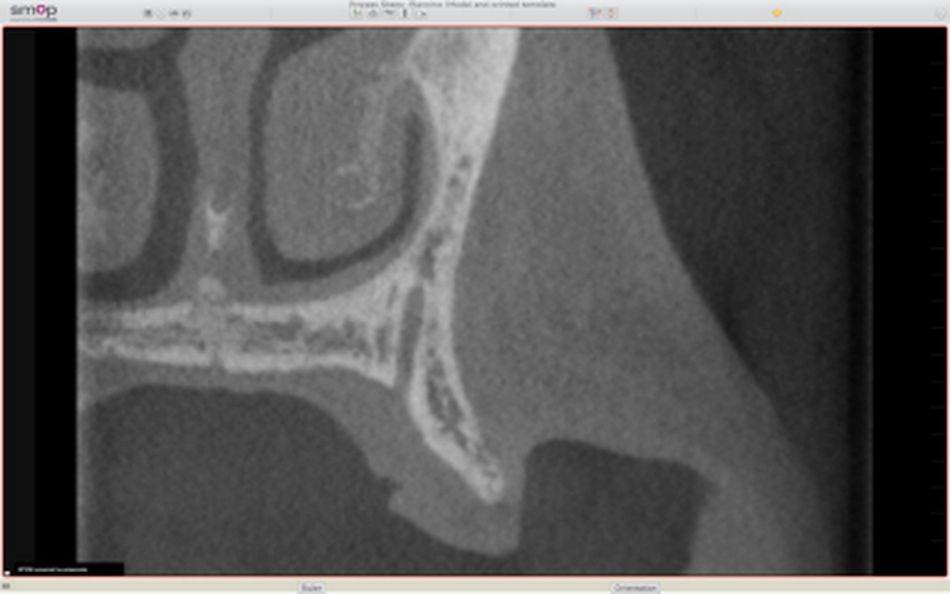

To better assess the bony situation at site 24, a CBCT radiograph was performed. It revealed a very thin bone crest with a width of approximately 3mm and a height of 16mm (Fig. 3). Several treatment options were discussed: